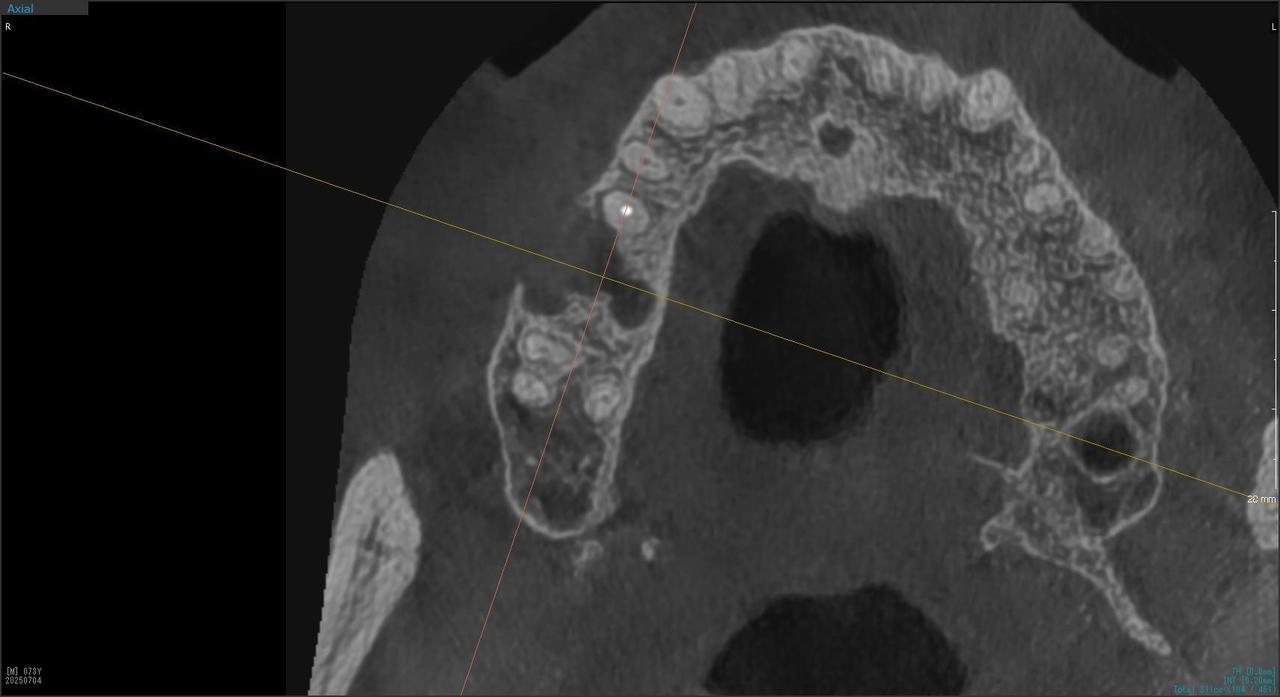

3.左上5の頬・舌側の大幅な骨欠損と上顎既存骨3mmまでの骨欠損がおこった症例に対しておこなったインプラント治療

Before

枚方市のインプラントの症例

After

I・K 様 女性 40代

症状としては、左上5の歯根破折を起こしていたため、排膿と自発痛をみとめた。それにともなう骨の大きな欠損。

治療法としては、炎症が強くたったためと、炎症による頬側側歯肉の退縮を認めていたために、まず、抜歯を行い上顎洞内及び歯抜した周囲組織の回復を試みた。その後、患者様がインプラント治療を希望したため、薄い上顎骨に対しては、グラフトレスサイナスリフト、骨欠損部には、人口骨補填を行い、頬側歯肉が退縮していることを改善するために、1回法でリーリングアバットメントを装着して、アバットメントの上に歯肉が覆うようにして、歯肉のボリューム回復を行った。2か月後、インプラントが骨と結合していることを確認して、光学印象を行い、2週間後にアバットメントとジルコニアクラウンを装着した。

治療結果としては、大幅な骨欠損があったが、グラフトレスサイナスリフトと骨欠損部に人工骨を補填して、抜歯した穴が自然に治る状態にしたことで、2か月半という短い期間での治療を完了することができた。(仮に、GBRや通常のサイナスリフトでの治療を行っていたら、最低でも1年は、かかってくる治療であると考える。)また、今回は、即時荷重を避け、1回法での治療を行ったことで、噛めない期間ができてしまったが、1回法で行ったことにより、歯肉のボリュームが増して、ブラッシングがしやすい口腔内環境にすることができた。低侵襲で、短時間で、治療を終えることができ、また、審美性・機能性の回復も行えたことができた。

治療の期間・回数:約2.5か月、6回

治療の価格:368,500円(税込)

治療費の内訳:インプラント基本料(フィックスチャー及び手術費用、投薬費用、レントゲン費用、インプラント上部費用(アバットメントおよびジルコニアクラウンの費用用)330000円(税込み)。オプション費用グラフトレスサイナスリフト費用プラス人工骨費用 38500円(税込み

治療のリスクや副作用:手術後に、痛みや腫れ、出血、合併症などを引き起こす可能性があります。噛む感覚がご自身の歯と異なる場合があります。見た目がご自身の歯と異なる場合があります。手術後にメインテナンスを継続しないと、インプラントが抜け落ちる可能性があります。